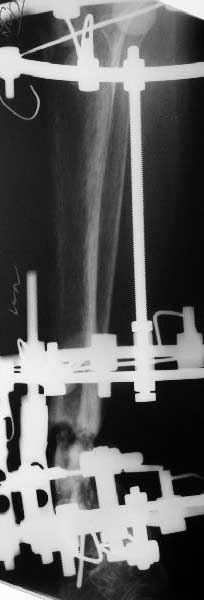

Re: Еще несращение distal tibia

В общем, начали c аппарата - нложили, малоберцовую внизу пересекли, выбрали люфт, раз дальше сопротивление пошло - выведем постепенно.

Картинки приложены. Жду комментариев.